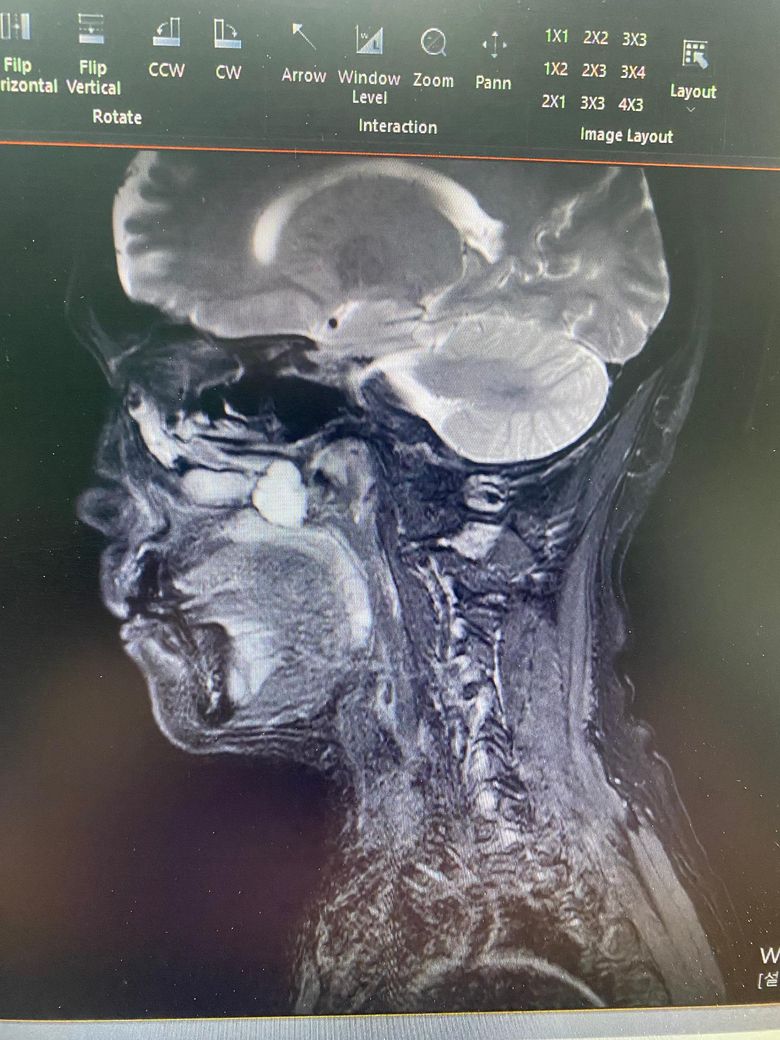

다른 질병으로 치과 진료중 상악골 후방에 물혹이 있다는걸 발견했습니다.

구강안면외과에서 수술 권유를 받았는데 위치가 너무 어렵다고 하더라구요.

• 1번 째 사진